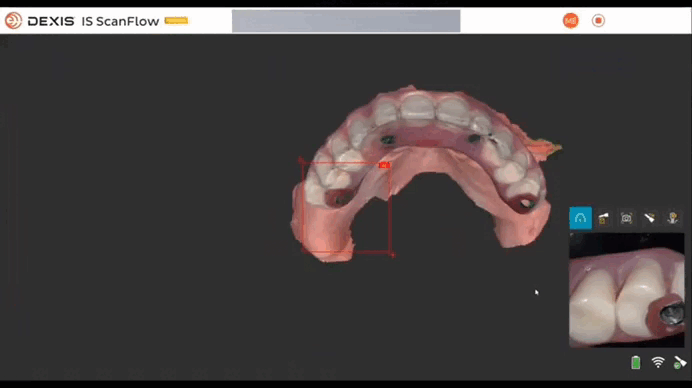

1. Сканирование анатомии с временными реставрациями

Сканирование анатомии проводится сначала на верхней, а затем на нижней челюсти. В данном случае сканирование осуществлялось по малой дуге: сначала оральная поверхность, затем – окклюзионная, в конце – вестибулярная. После сканирования верхней и нижней челюстей проводится фиксация окклюзии по трем точкам. Программное обеспечение IS ScanFlow также позволяет зафиксировать несколько разных окклюзий (более трех).

Верхняя челюсть

Нижняя челюсть